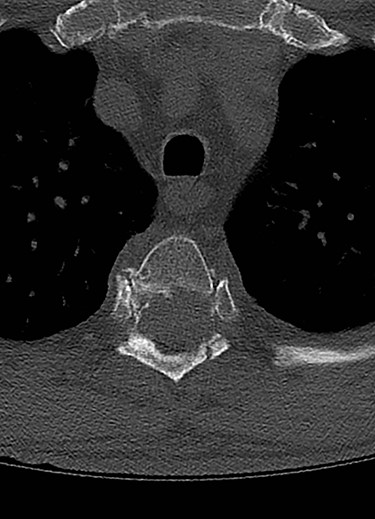

Spinal images are presented in Figs 1–6. Cross-sectional imaging revealed no other neoplastic lesion. He received dexamethasone 10 mg bolus then 4mg four times daily with appropriate proton pump inhibitor coverage. Due to no distinguishable major arterial feeder upon review of the imaging jointly with the neuroradiologist, pre-operative embolization was not attempted. The following morning, he underwent posterolateral right costotransversectomy, ligation of the ipsilateral T4 nerve root, T4 vertebrectomy and insertion of an expandable titanium cage with T1–T7 pedicle screw fixation (Figs 7 and 8). Post-operatively his pain improved to VAS 2/10 and motor power in his left lower limb improved to MRC grade 4/5. The patient was discharged home Day 10 post-admission with physiotherapy.

The patient presented with thoracic kyphosis and clinical evidence of mechanical pain. The radiological images showed evidence of three-column involvement of the T4 lytic lesion. Adjacent bilateral pedicle fracture of T5 offered no additional structural support and therefore this degree of deformity was not surprising. This spinal instability neoplastic score (SINS) [3] of 14/18 and grade 3 epidural spinal cord compression (ESCC) [2] were in support of surgical decompression and stabilization [2, 3]. A number of approaches were considered including anterior transcavitary, posterolateral extrapleural approaches and posterior decompression and instrumentation, with or without insertion of expandable titanium cage [1]. Laminectomy alone or with radiotherapy was not an option in this case as it would have offered very little decompression of this anteriorly compressing lesion as well as exacerbate the deformity by further sacrificing the posterior elements, thereby offering no contribution at structural stability.